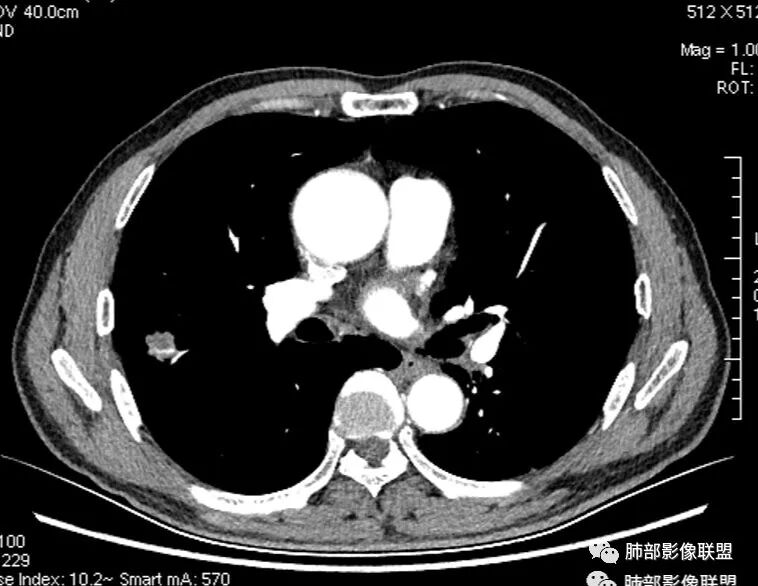

影像学改变:

1.右肺上叶后段类圆形结节影,密度不均,有坏死空洞,坏死比较彻底,内外壁都较清楚。

2.病灶有浅切迹,没有深分叶,毛刺大多细长且柔软。

3.可见棘状突起及胸膜牵拉,但未见胸膜凹陷。

什么意思?结节影有牵拉的动作,但似乎“出工不出力”,收缩力羸弱!

4.病灶轻到中度强化。病灶内血管走行较完好,病灶旁血管局部显示粗大。

5.支气管关系不确定。

6.灶周见小结节影(卫星灶),边界不甚清晰。